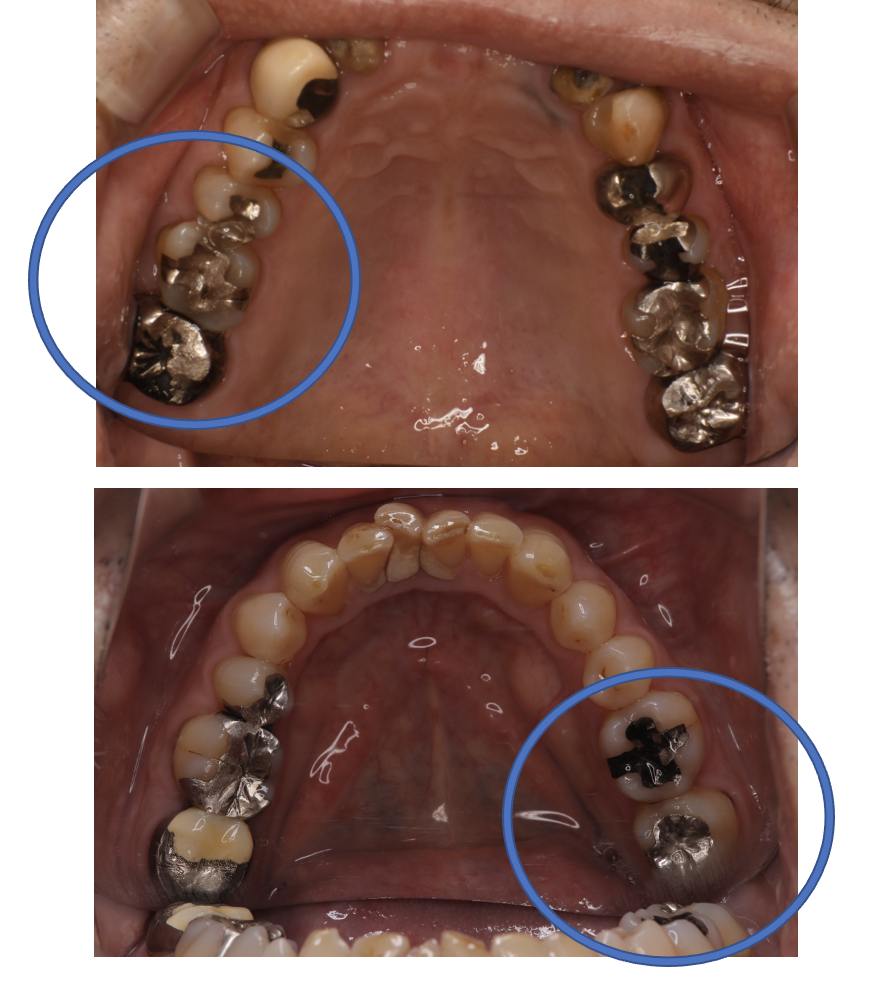

Before

| 備考 | 院長より 銀歯の内部に虫歯が進行してしまっていたケースです。中を開けて見てみると、外から想像するよりもはるかに虫歯が広がってしまっていました。幸運にも神経を保存できたので、生きた臓器としてまだ使うことが可能です。残存歯質がかなり薄く弱くなってしまったので、ジルコニアで被せて守ってあげています。しっかりとした治療ができたので、まだまだ長く使っていけるでしょう。 |